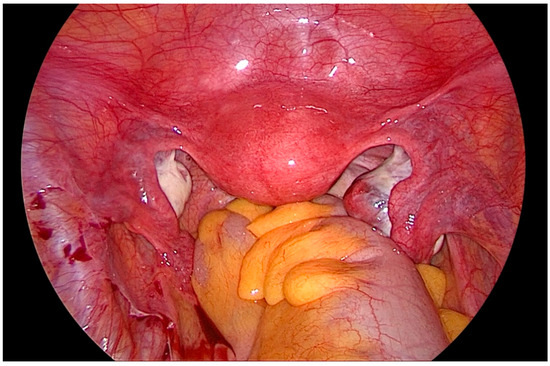

After gaining access to the peritoneal cavity laparoscopically (Figure 1), the cavity is thoroughly investigated for endometriotic cysts, spots, and adhesions. If an endometriotic ovarian cyst is found, it is excised. If endometriotic spots or nodules are found underneath the ovary on the ovarian fossa, or uterosacral ligaments, the ipsilateral ovary is suspended to the anterior abdominal wall (Figure 2). A straight needle with a single monofilament non-absorbable thread is passed through the lower anterior abdominal wall. Prior to insertion of the needle, the inferior epigastric vessels should be located to avoid injury and hematoma formation. The needle is retrieved intra-corporeally by grasping it using a laparoscopic needle holder. It is then passed from the medial side of the ovary through the ovary into the abdominal wall close to the point where it was introduced. At this step also, it is essential to pay attention to the inferior epigastric vessels once more. The needle is then pulled out from the abdominal wall using a hemostat forceps. The two ends of the thread are tied extra-corporeally over a compressor gauze on the abdominal wall, with some tension, thus suspending the ovary to the abdominal wall with the medial side of the ovary apposed to the peritoneum of the anterior abdominal wall (Video S1).

Figure 1. Laparoscopic view of the pelvis, depicting the ovaries hampering vision and access to the lateral pelvic wall.